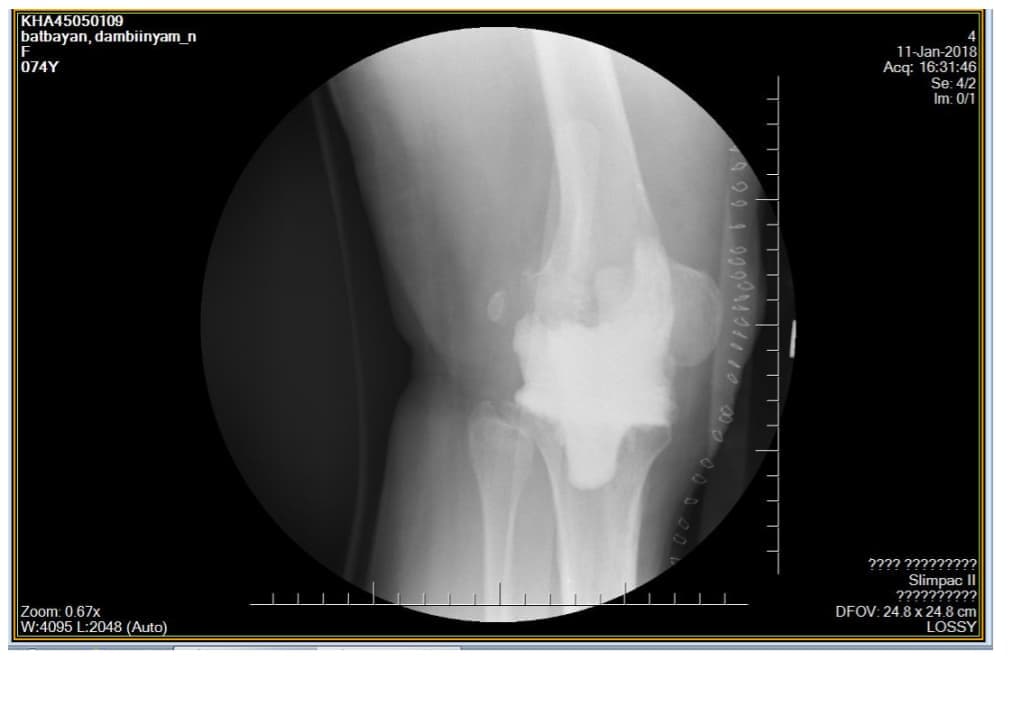

Өвчтөн: M, 73 настай, эмэгтэй

Урьд нь хийгдсэн мэс заслын түүх: 2013 онд өвдөгний хиймэл үе суулгах мэс засал хийлгэсэн. Мэс заслын дараа халдварын хүндрэл гарсан.

Хоёрдахь мэс засал: Хиймэл үеийг авч, оронд нь антибиотиктэй цемент, төмөр бэхэлгээ хийсэн. Мэс заслын дараа үрэвсэл намдсан. Үрэвслийн улмаас ясны том хэмжээний дутмагшил үүссэн.

Сэргээн засах мэс засал: Зүүн дунд чөмөг-өвдөгний хавдрын протез суулгах мэс засал

Эмнэлэгт хэвтсэн ор хоног: 10

Үе дайрсан ясны анхдагч хавдар, ясны дутмагшлын үед хийгдэх мэс засалimage13

Зураг 1. Мэс заслын дараах рентген зураг: артродез буюу “үегүйжүүлэх” мэс засал.